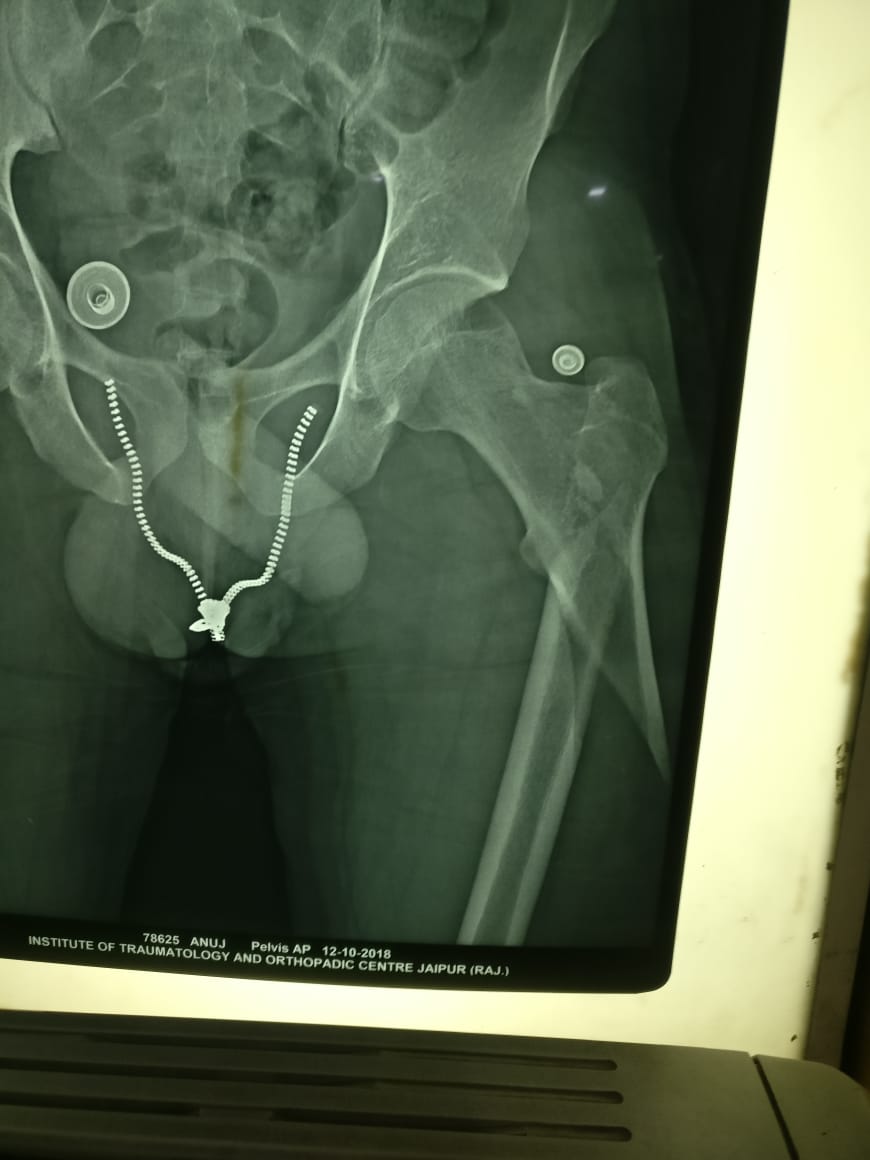

Acetabulm fracture fixetion